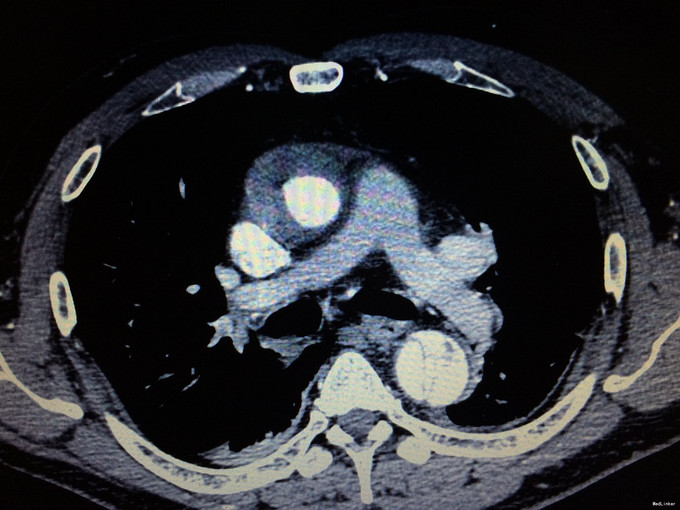

患者男,45岁,主因胸痛2小时入院

CT:升主动脉环形增厚,未见强化;主动脉弓和降主动脉形成动脉夹层,可见内膜片

主动脉夹层合并主动脉壁内血肿 治疗:急诊手术:升主动脉置换+全弓置换+支架象鼻植入

该患者为A型主动脉夹层,同时还合并升主动脉壁内血肿,这是很罕见的。有人认为主动脉壁内血肿可能是夹层的原因,但是根据近几年的研究,已经把AMI独立为一种疾病了,并且把AMI,AD和PAU统称为急性主动脉综合征。所以胸痛病人,一定要鉴别是ACS,还是AAS。如果是AAS,你给他抗血小板,将是致命的错误!这种病有多危险呢?每一个小时死亡1%,2天后死一半。